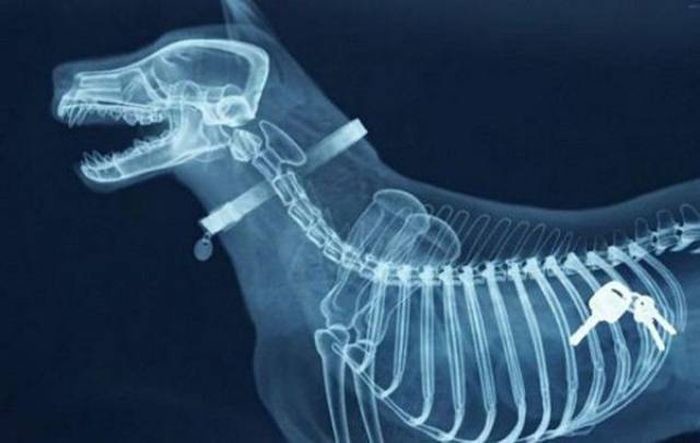

Предметы, которые не очень хочется видеть внутри себя

Под рентгеновскими лучами порой видны не только внутренние органы и кости, но и инородные тела, попавшие в организм

Истории попадания этих предметов в организм могут быть самыми невероятными и запутанными, но больше всего медиков интересует процесс их извлечения, впрочем, в этом заинтересованы и сами пациенты, допустившие нечто подобное со своим телом.